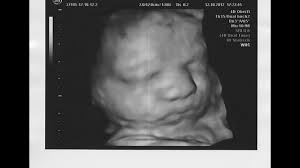

3d Ultraschall 22 27 Ssw 1111 Abonnenten Special Youtube